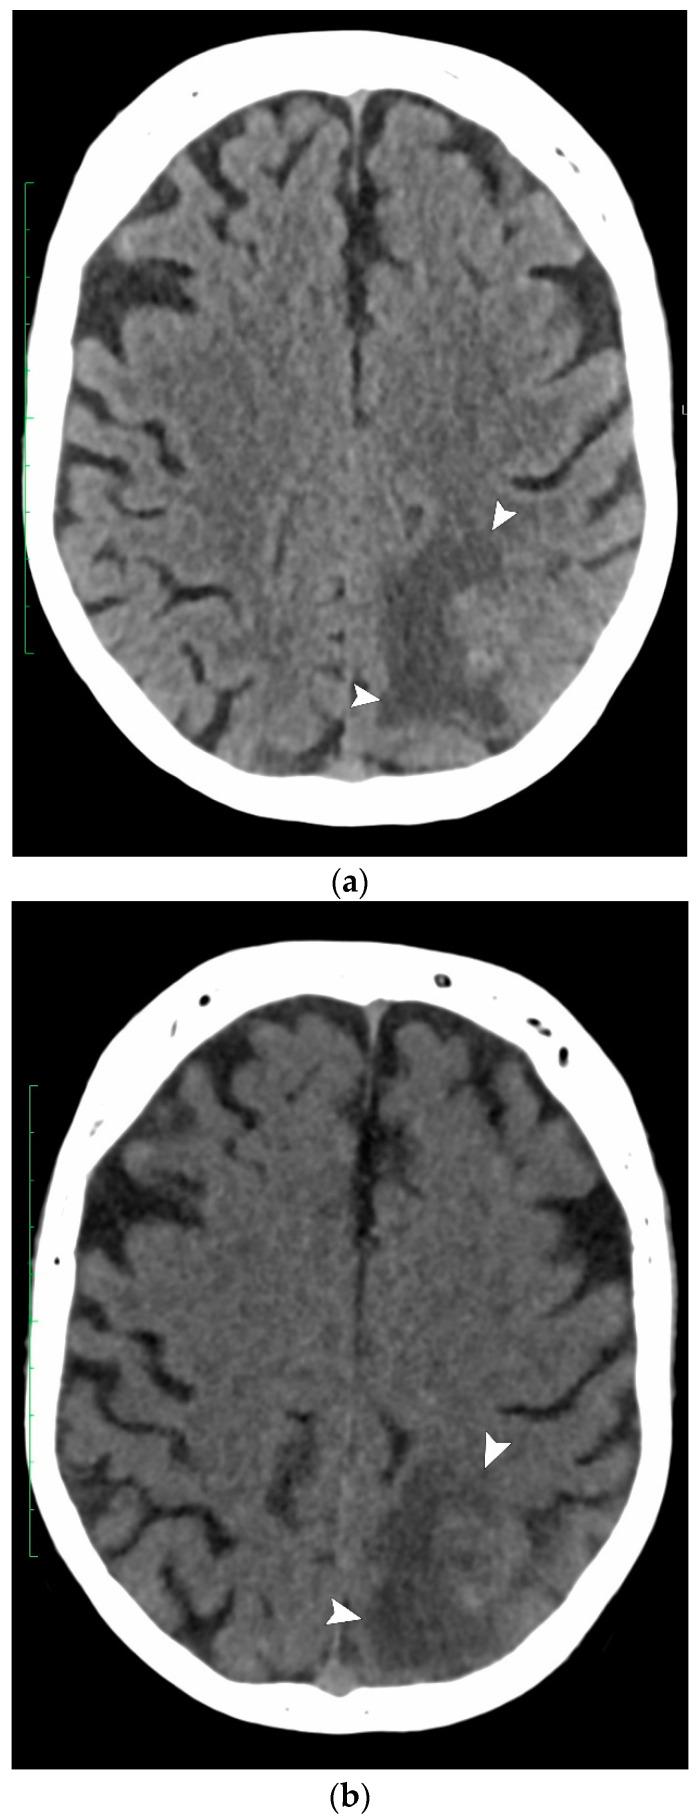

We aimed to evaluate whether virtual non-contrast cerebral computed tomography (VNCCT) reconstructed from intravenous contrast-enhanced dual-energy CT (iv-DECT) could replace non-contrast CT (NCCT) in patients with suspected acute cerebral ischemia. This retrospective study included all consecutive patients in whom NCCT followed by iv-DECT were performed for suspected acute ischemia in our emergency department over a 1-month period. The Alberta Stroke Program Early CT Score (ASPECTS) was used to determine signs of acute ischemia in the anterior and posterior circulation, the presence of hemorrhage, and alternative findings, which were randomly evaluated via the consensus reading of NCCT and VNCCT by two readers blinded to the final diagnosis. An intraclass correlation between VNCCT and NCCT was calculated for the ASPECTS values. Both techniques were evaluated for their ability to detect ischemic lesions (ASPECTS <10) when compared with the final discharge diagnosis (reference standard). Overall, 148 patients (80 men, mean age 64 years) were included, of whom 46 (30%) presented with acute ischemia, 6 (4%) presented with intracerebral hemorrhage, 11 (7%) had an alternative diagnosis, and 85 (59%) had no pathological findings. The intraclass correlation coefficients of the two modalities were 0.97 (0.96-0.98) for the anterior circulation and 0.77 (0.69-0.83) for the posterior circulation. The VNCCT's sensitivity for detecting acute ischemia was higher (41%, 19/46) than that of NCCT (33%, 15/46). Specificity was similar between the two techniques, at 94% (97/103) and 98% (101/103), respectively. Our results show that VNCCT achieved a similar diagnostic performance as NCCT and could, thus, replace NCCT in assessing patients with suspected acute cerebral ischemia.

我们旨在评估从静脉注射对比剂的双能量CT(iv-DECT)重建的虚拟非增强脑计算机断层扫描(VNCCT)能否替代疑似急性脑缺血患者的非增强CT(NCCT)。这项回顾性研究纳入了在1个月内于我们急诊科因疑似急性缺血而先后进行NCCT和iv-DECT检查的所有连续患者。使用阿尔伯塔卒中项目早期CT评分(ASPECTS)来确定前循环和后循环中急性缺血的征象、出血情况以及其他发现,由两名对最终诊断不知情的读者通过对NCCT和VNCCT的一致性解读进行随机评估。计算VNCCT和NCCT的ASPECTS值之间的组内相关性。将两种技术与最终出院诊断(参考标准)进行比较,评估它们检测缺血性病变(ASPECTS<10)的能力。总体而言,共纳入148例患者(80例男性,平均年龄64岁),其中46例(30%)出现急性缺血,6例(4%)出现脑出血,11例(7%)有其他诊断,85例(59%)无病理发现。两种模式在前循环的组内相关系数为0.97(0.96 - 0.98),后循环为0.77(0.69 - 0.83)。VNCCT检测急性缺血的敏感性高于NCCT,分别为41%(19/46)和33%(15/46)。两种技术的特异性相似,分别为94%(97/103)和98%(101/103)。我们的结果表明,VNCCT在诊断性能上与NCCT相似,因此在评估疑似急性脑缺血患者时可以替代NCCT。